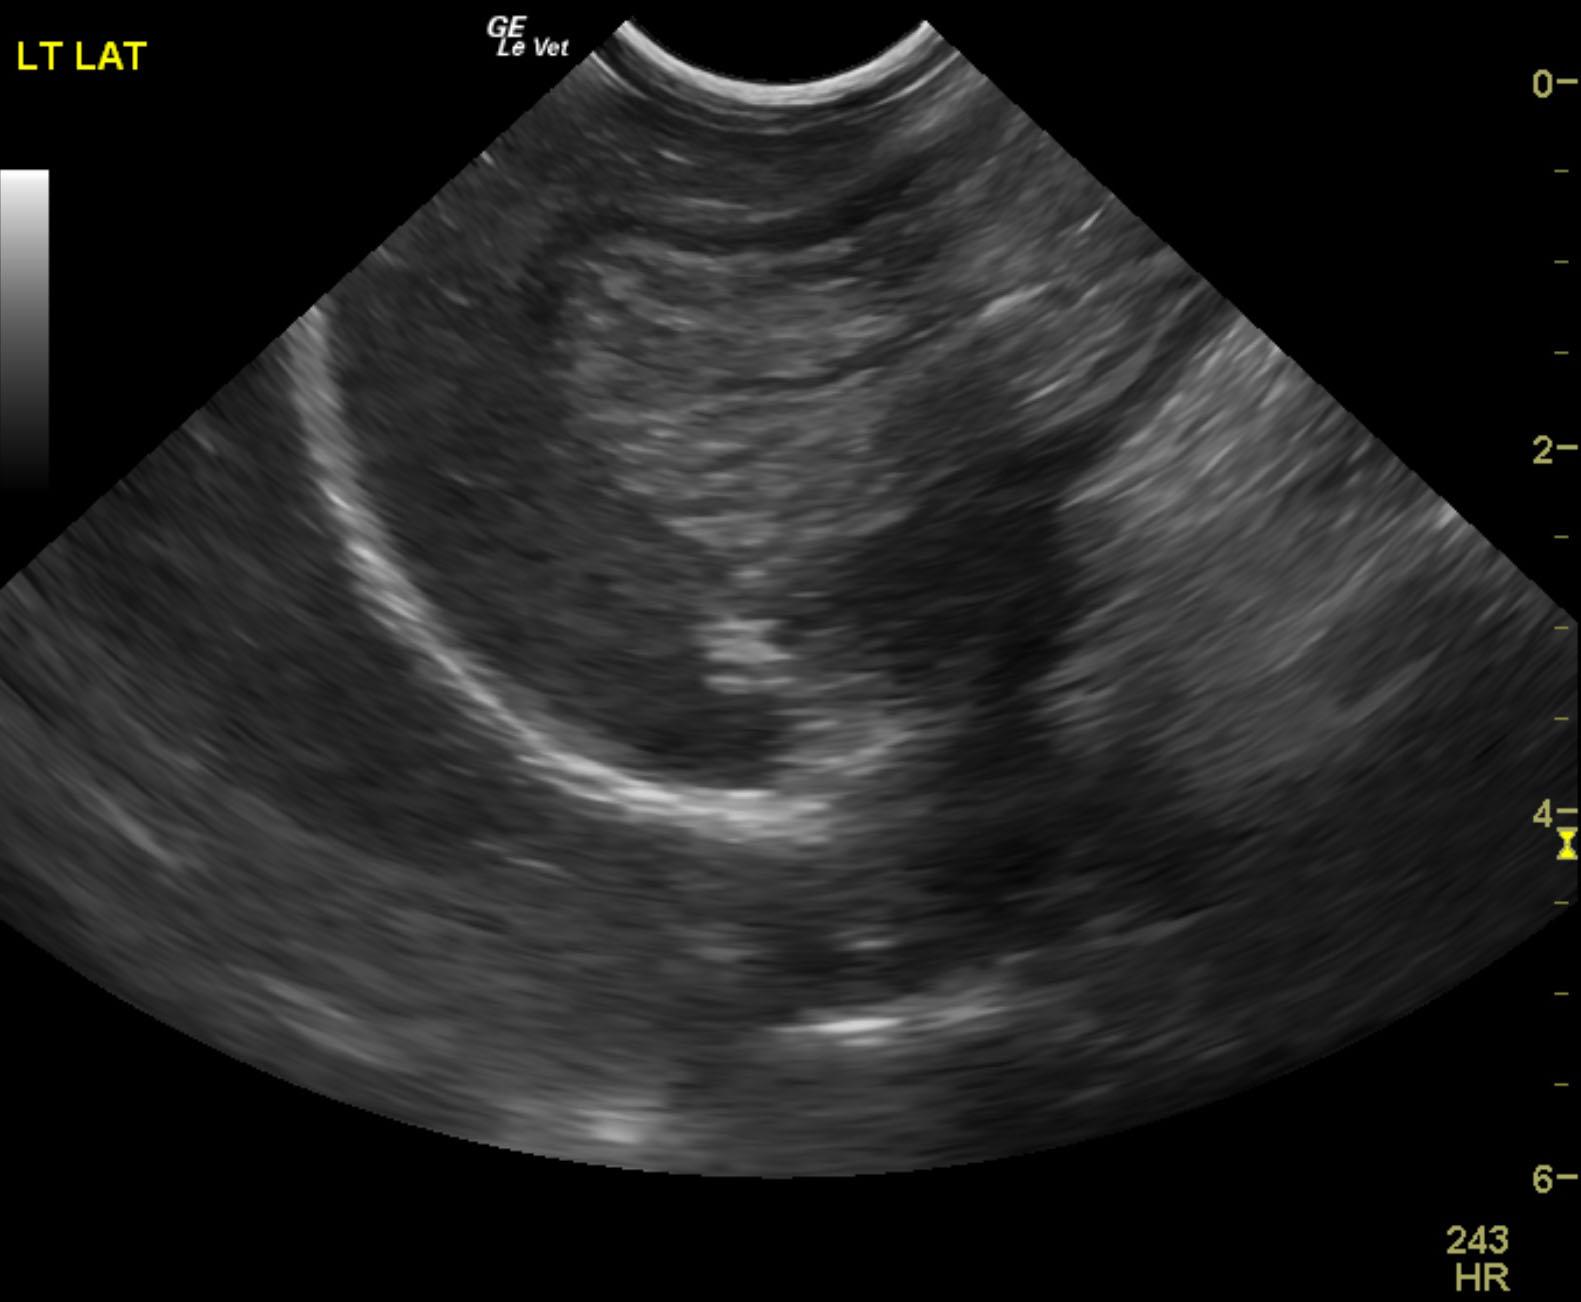

The patient is a 13 year old spayed female Dachshund dog which was presented for four days of anorexia and vomiting. She was given Cerenia, which helped, but still had ileus. Dog has vomited carpet material in past. Spec cPL was normal. Radiographs revealed dilated intestine, which appeared to be colon and cecum.